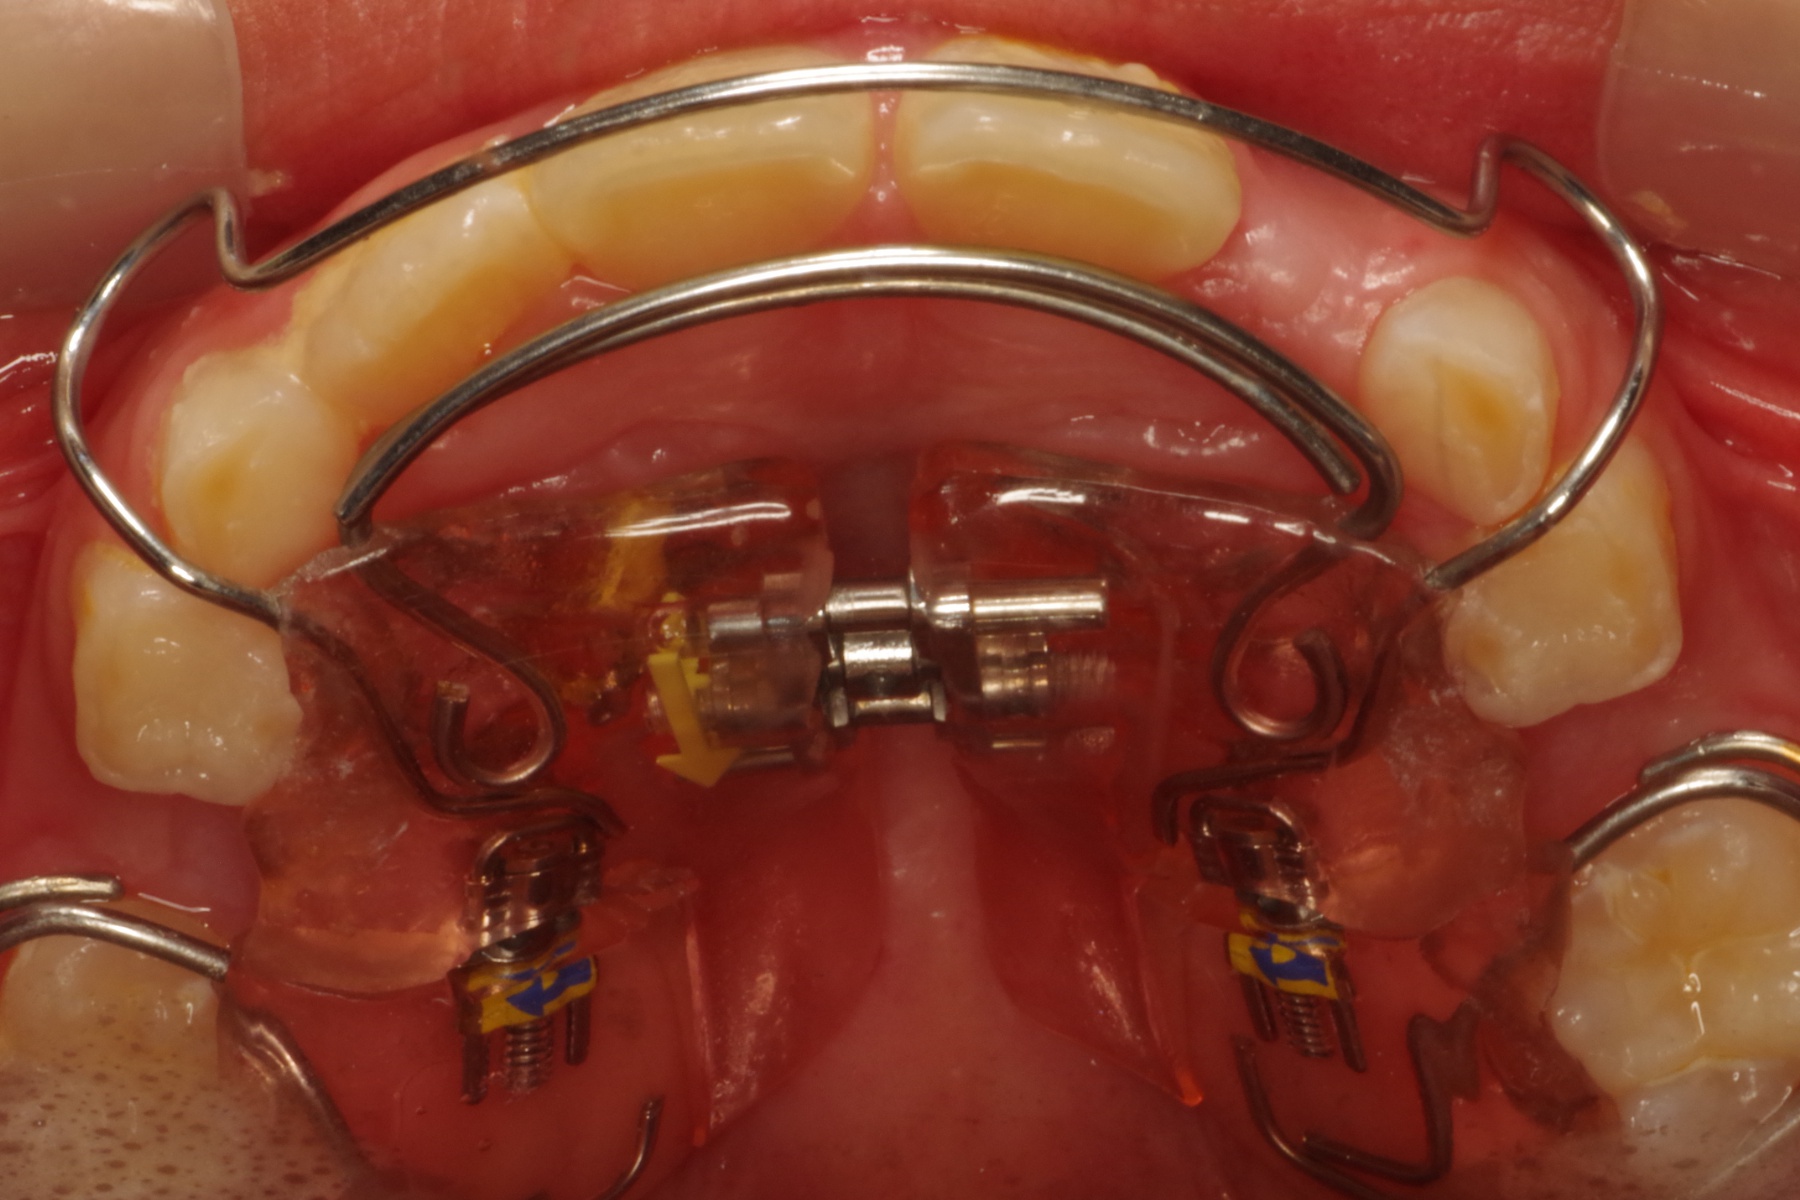

当医院ではお子様の矯正に顎の成長をサポートするような装置を使い、歯ならびを矯正します。

取り外し出来る装置のため、お子様の負担も少なく、気軽に使用できます。

当医院では歯並びだけでなく咬み合わせの確認も行っていきます。

適応年齢は小学生~中学生ですが、それ以前の年齢のお子様も定期健診で様子を診ていきますのでお気軽にご相談下さい。